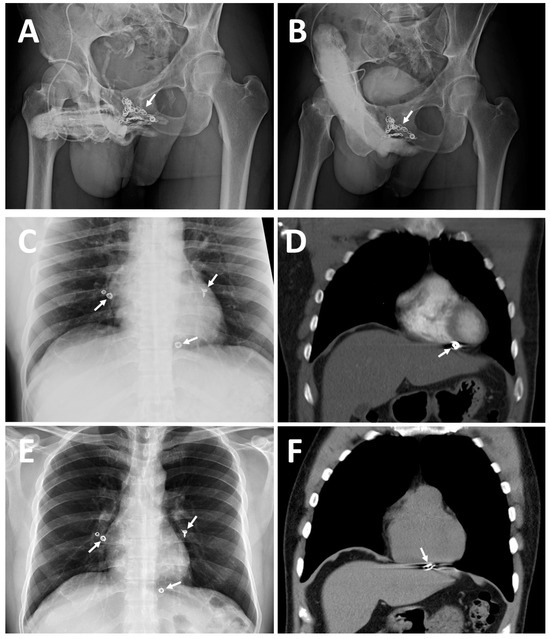

| ED a | 2008 | Early detumescence of rigid erection, position-dependent | A multiplanar diagnosis workup showed a veno-occlusive dysfunction. |

| CE(I) b | 2010 | Same | Acute chest pain was caused by the migration of a dumbbell-shaped coil to the right pulmonary artery. |

| CE(II) c | November 2012 | Same | A tapeworm-shaped coil was noted in the region of the right iliac vein at 90 degrees to the venous channel. |

| CE(III) d | May 2014 | Same | A pigtail-shaped coil was shown at the left internal pudendal vein level at 90 degrees to the venous channel. |